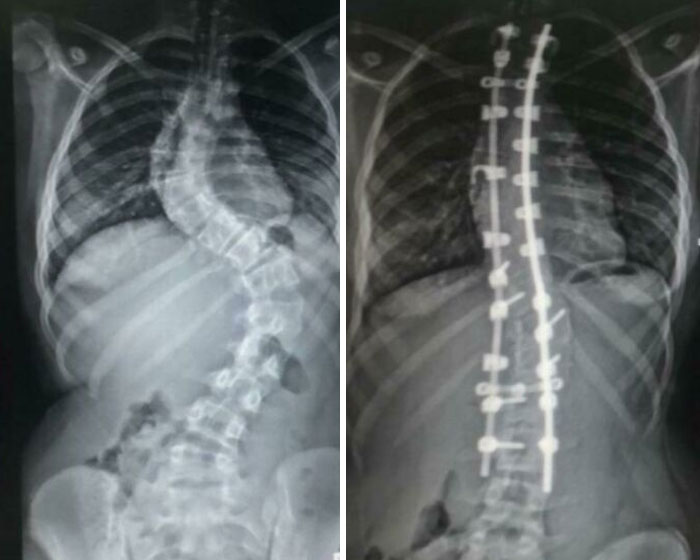

Mi columna antes y después de la operación